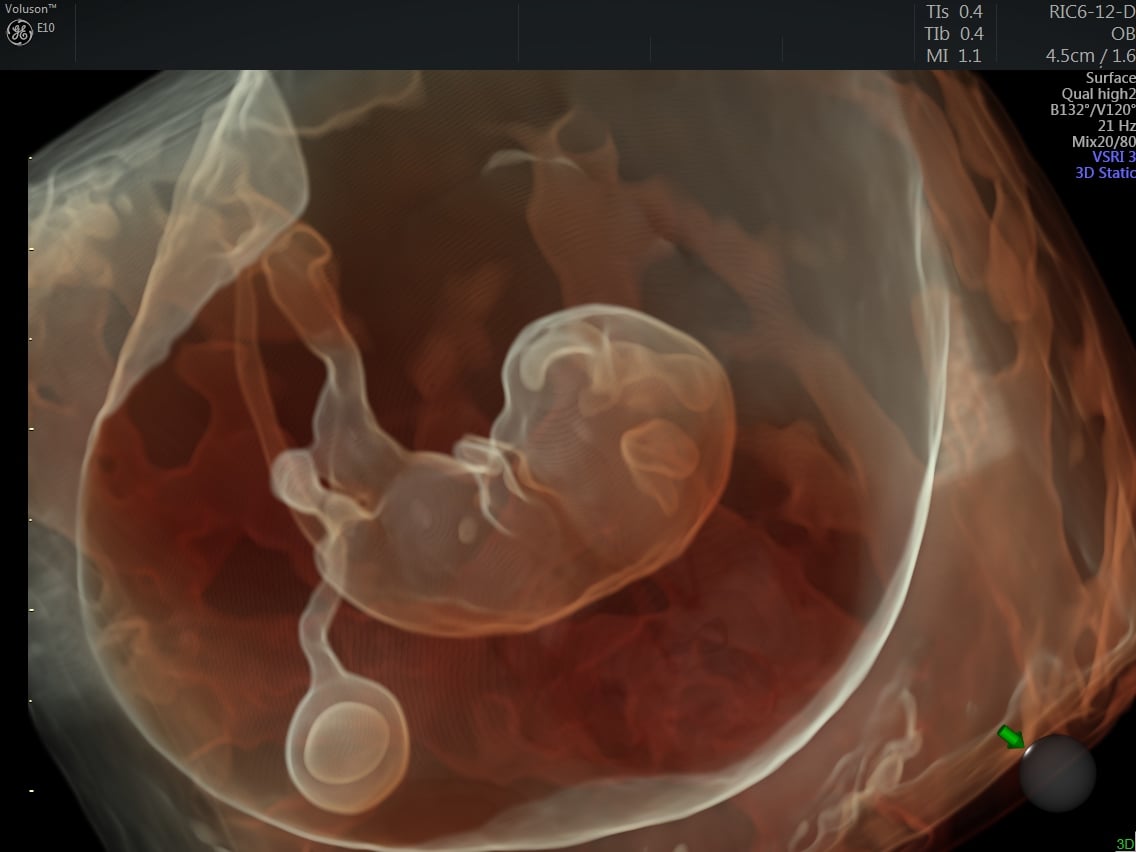

3D-4D ultrasound of a fetus imaged with a GE Volusion E10 system. It shows the yoke sac.